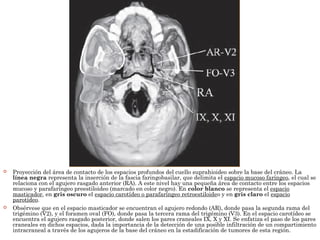

 Proyección del área de contacto de los espacios profundos del cuello suprahioideo sobre la base del cráneo. La

línea negra representa la inserción de la fascia faringobasilar, que delimita el espacio mucoso faríngeo, el cual se

relaciona con el agujero rasgado anterior (RA). A este nivel hay una pequeña área de contacto entre los espacios

mucoso y parafaríngeo preestiloideo (marcado en color negro). En color blanco se representa el espacio

masticador, en gris oscuro el espacio carotídeo o parafaríngeo retroestiloideo y en gris claro el espacio

parotídeo.

 Obsérvese que en el espacio masticador se encuentran el agujero redondo (AR), donde pasa la segunda rama del

trigémino (V2), y el foramen oval (FO), donde pasa la tercera rama del trigémino (V3). En el espacio carotídeo se

encuentra el agujero rasgado posterior, donde salen los pares craneales IX, X y XI. Se enfatiza el paso de los pares

craneales en dichos espacios, dada la importancia de la detección de una posible infiltración de un compartimiento

intracraneal a través de los agujeros de la base del cráneo en la estadificación de tumores de esta región.